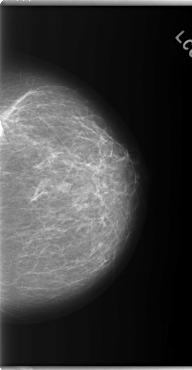

C_0147_1.LEFT_MLO

C_0147_1.LEFT_CC

LEFT_MLO LINES 5896 PIXELS_PER_LINE 3360 BITS_PER_PIXEL 12 RESOLUTION 50 NON_OVERLAY